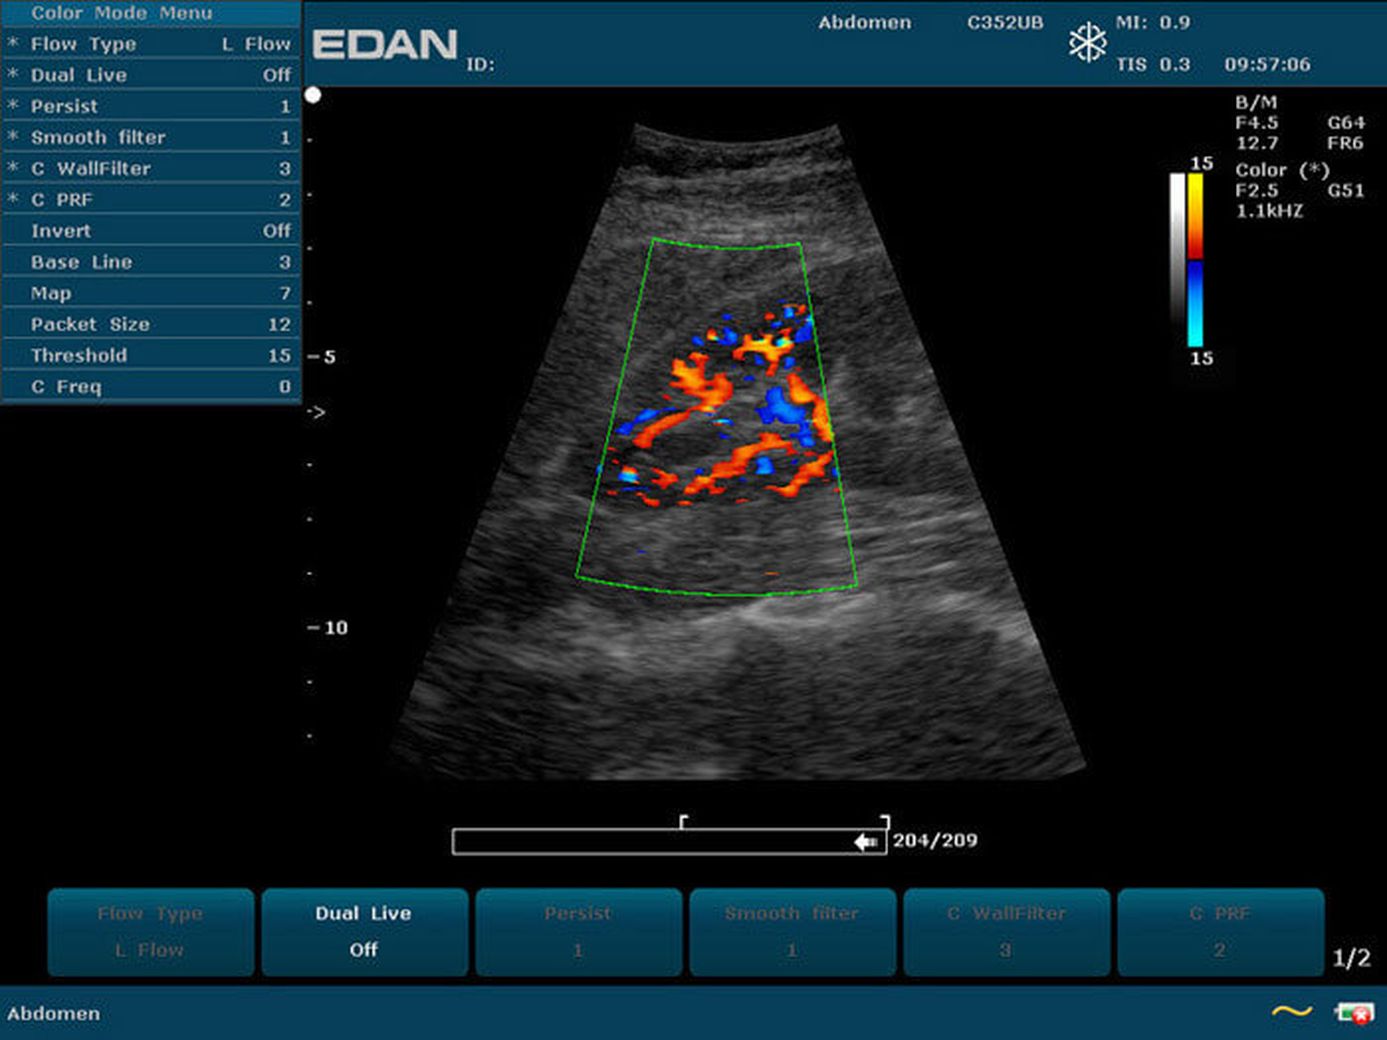

Прибор u2 143 фото